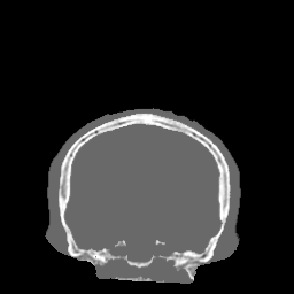

Model-based treatment planning for transcranial ultrasound therapy typically involves mapping the acoustic properties of the skull from an x-ray computed tomography (CT) image of the head. Here, three methods for generating pseudo-CT images from magnetic resonance (MR) images were compared as an alternative to CT. A convolutional neural network (U-Net) was trained on paired MR-CT images to generate pseudo-CT images from either T1-weighted or zero-echo time (ZTE) MR images (denoted tCT and zCT, respectively). A direct mapping from ZTE to pseudo-CT was also implemented (denoted cCT). When comparing the pseudo-CT and ground truth CT images for the test set, the mean absolute error was 133, 83, and 145 Hounsfield units (HU) across the whole head, and 398, 222, and 336 HU within the skull for the tCT, zCT, and cCT images, respectively. Ultrasound simulations were also performed using the generated pseudo-CT images and compared to simulations based on CT. An annular array transducer was used targeting the visual or motor cortex. The mean differences in the simulated focal pressure, focal position, and focal volume were 9.9%, 1.5 mm, and 15.1% for simulations based on the tCT images, 5.7%, 0.6 mm, and 5.7% for the zCT, and 6.7%, 0.9 mm, and 12.1% for the cCT. The improved results for images mapped from ZTE highlight the advantage of using imaging sequences which improve contrast of the skull bone. Overall, these results demonstrate that acoustic simulations based on MR images can give comparable accuracy to those based on CT.